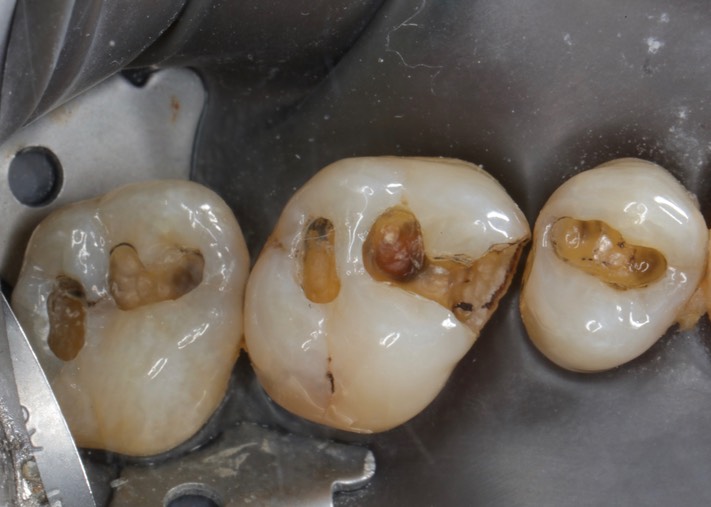

Mark Chun #13,14,15 amalgam removal